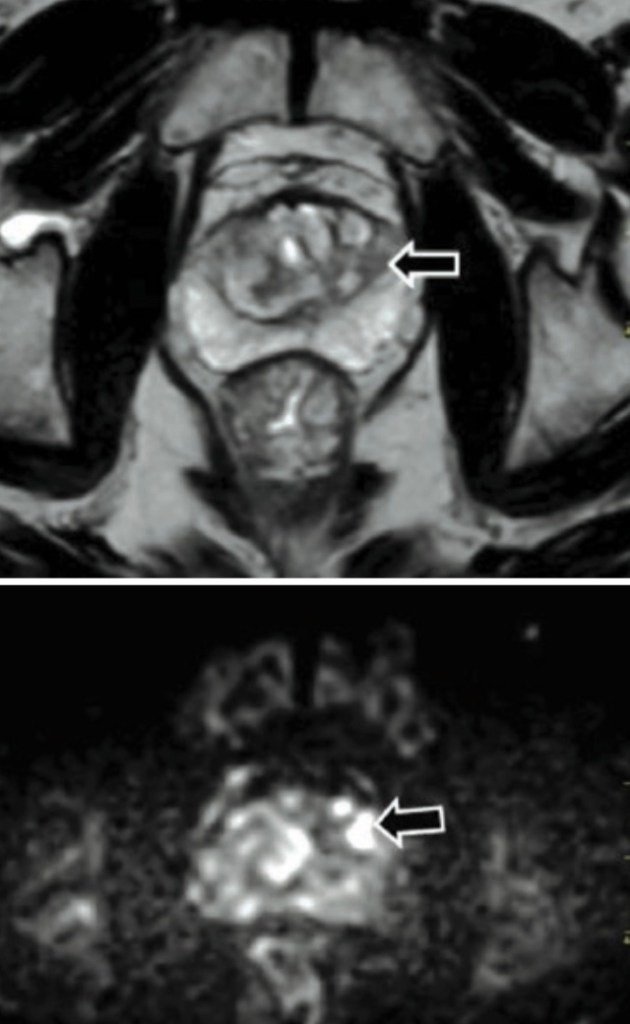

Aprovechando el poder que tiene la resonancia magnética y la facilidad de la misma para que evaluar la periferia de la glándula prostática, desde hace algunos años viene siendo utilizada esta herramienta tecnológica con el objetivo de mejorar lo resultados de las biopsias prostáticas.

El examen nos permite también identificar zonas inflamatorias que podrían confundirse con focos de cáncer, con la característica de tener valores bajos de parámetro DWI. La facilidad de obtener imágenes contrastadas permite localizar zonas de mas alta chance tumoral, con mayor sospecha de celularidad y sobre todo con pronósticos de gleason más altos dependiendo la imagen obtenida en la resonancia biparamétrica.

El utilizar la resonancia magnética previa a la biopsia puede disminuir en forma considerable el número de muestras y, por consiguiente, impactar en la morbilidad del procedimiento, además de elevar la certeza histológica de neoplasia con respecto a otros procedimientos que no usan IRM como guía.